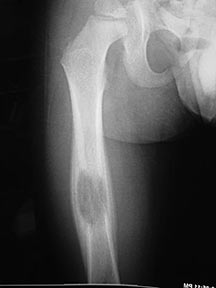

- May arise from any bone and any site within a bone (epiphyseal, metaphyseal, diaphyseal)

- Radiographically variable appearance: may appear benign (geographic) or malignant (permeative or moth eaten)

Sites:

- Flat Bones (most common—70%)

- Femur